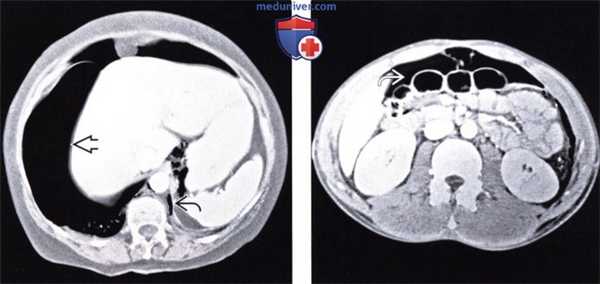

(Слева) При аксиальной КТ с контрастом у молодою человека, находящегося на ИВЛ после аварии на мотоцикле, выявлен напряженный пневмоторакс с правой стороны и малый пневмоторакс слева. Газ под давлением распространяется вдоль около-диафрагмальной жировой клетчатки.

(Справа) На аксиальном КТ срезе у этого же пациента визуализируется внепросветный воздух из грудной полости, распространяющийся в брюшную полость, очерчивающий контуры петель кишечника. Нет повреждения органов брюшной полости. (Слева) На аксиальном КТ срезе (с контрастным усилением) у пожилого пациента, находящегося на вентиляции легких под давлением, с документированным двухсторонним пневмотораксом и пневмомедиастинумом, визуализируется газ, распространяющийся под давлением в брюшную полость, забрюшинное пространство и брыжейку.

(Справа) На аксиальном КТ срезе у этого же пациента визуализируется внепросветный воздух из грудной полости, распространяющийся в брюшную полость, очерчивающий контуры петель кишечника. Нет повреждения органов брюшной полости.